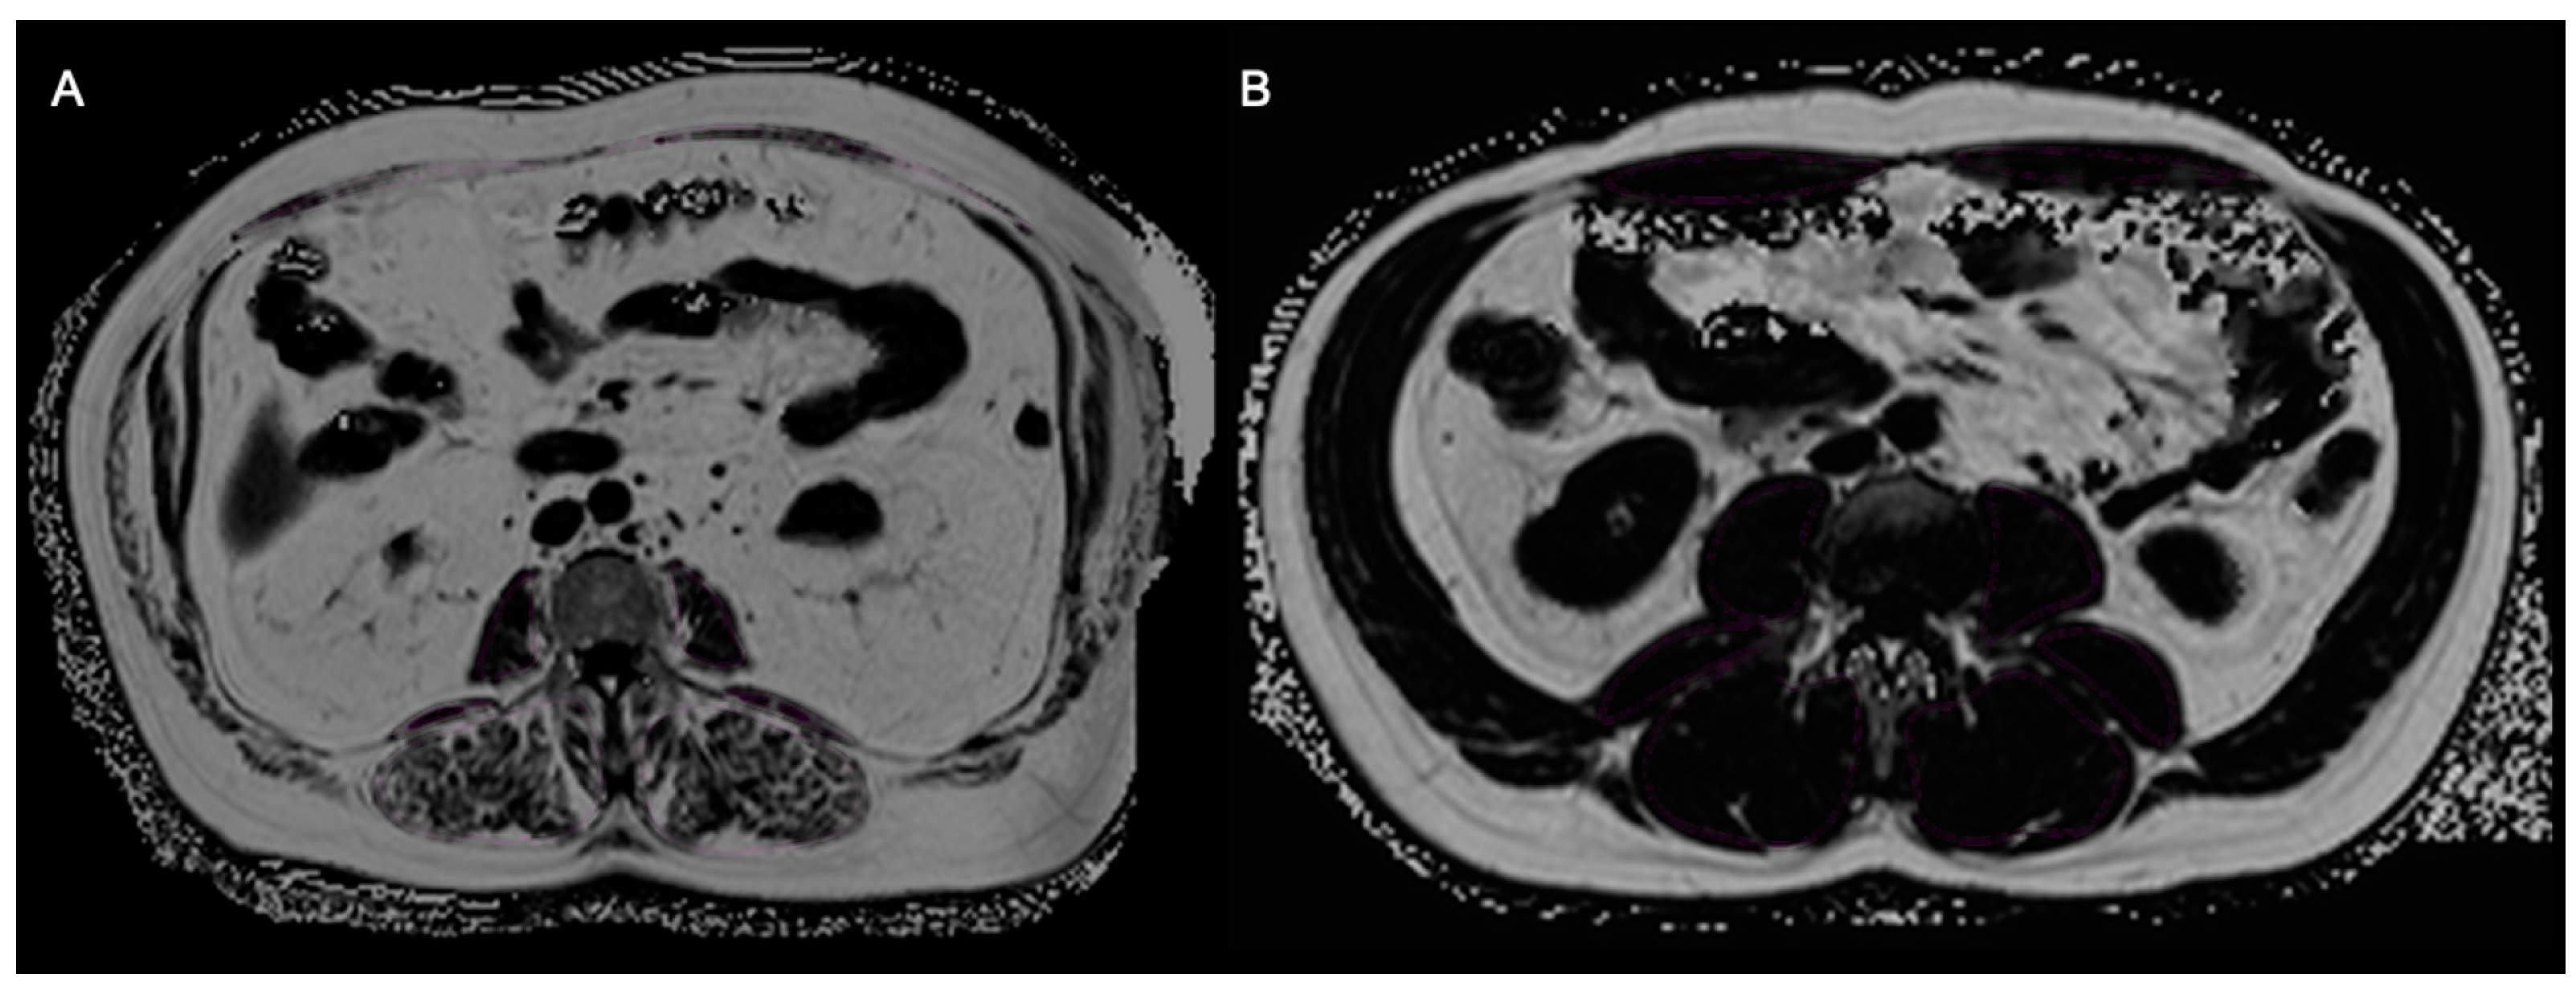

2.2.1. Bone Marrow Fat Fraction—Osteopenia

2.2.2. Skeletal Muscle Fat Fraction and Muscle Mass—Sarcopenia

2.2.3. Total, Visceral, and Subcutaneous Adipose Tissue—Adiposity